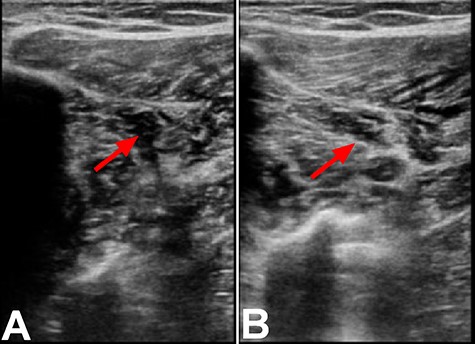

Twenty hours after discharge from the hospital, patient started to experience right calf pain and cramps. Patient attempted to elevate and ice the right leg as instructed by her surgeon; however, the pain was increasing resulting in admission to the emergency room. Upon presentation to the emergency room, she was able to put pressure on her leg but had difficulty ambulating. Ultrasound of the right lower extremity revealed thrombus within the anterior peroneal vein proximal to the mid-segment that did not extend to the popliteal vein (Fig. 1). Patient was given 4 mg ondansetron and 20 mg apixaban. Upon discharge, patient was given prescription of apixaban with plan of 10 mg BID for a week followed by 5 mg BID for 23 days.

Ultrasound of the right lower extremity within the anterior peroneal vein prior to compression (A) and with compression (B). Incomplete compression of the vein is suggestive of DVT as indicated by the red arrows.